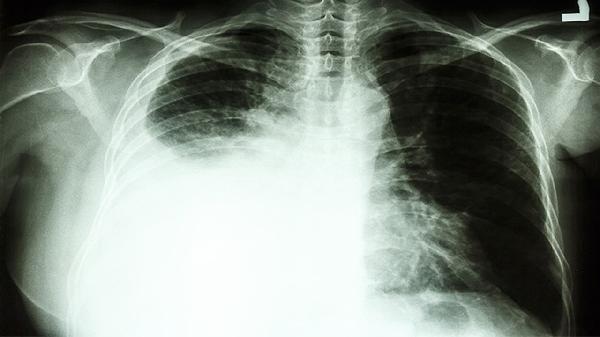

纵隔型肺癌在CT上多表现为与肺组织分界不清的肿块,可能伴有毛刺征或胸膜凹陷征,常见肺门淋巴结转移。纵隔肿瘤通常边界清晰,如胸腺瘤位于前纵隔,神经源性肿瘤多位于后纵隔,且与肺组织无直接关联。增强扫描时,纵隔肿瘤的强化模式因类型而异,如畸胎瘤可见脂肪密度,淋巴瘤多呈均匀强化。